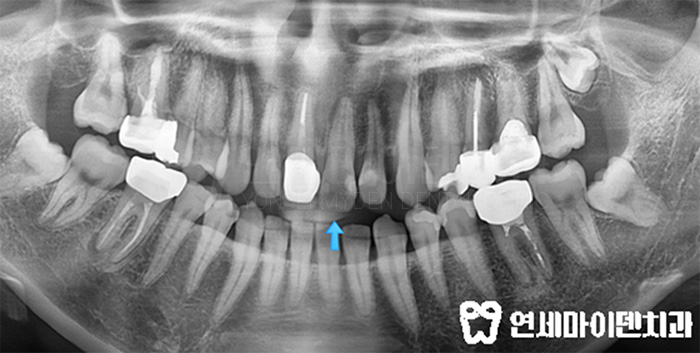

밥을 먹던 중 앞니가 부러져 타 병원에서 신경치료를 받고 계셨던 분입니다.

신경치료도 했던 치아인데,, 앞니 통증과 뿌리 염증이 지속되었습니다.

그래서 이 분은 앞니신경치료가 잘 되었는지도 검진하고

다시 재치료를 받고 크라운까지 마무리하기 위해서 오셨습니다.

연세마이덴치과는 당시 임시치아로만 마무리된 상태였는데 통증도 있어서

다시 한 번 내부를 들여다 보았습니다.